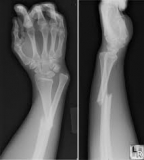

massage fractures

A fracture is a break in the continuity of the bone. In fractures, there are associated soft tissue injuries to the Ligaments, muscles, tendons, fascia, ...